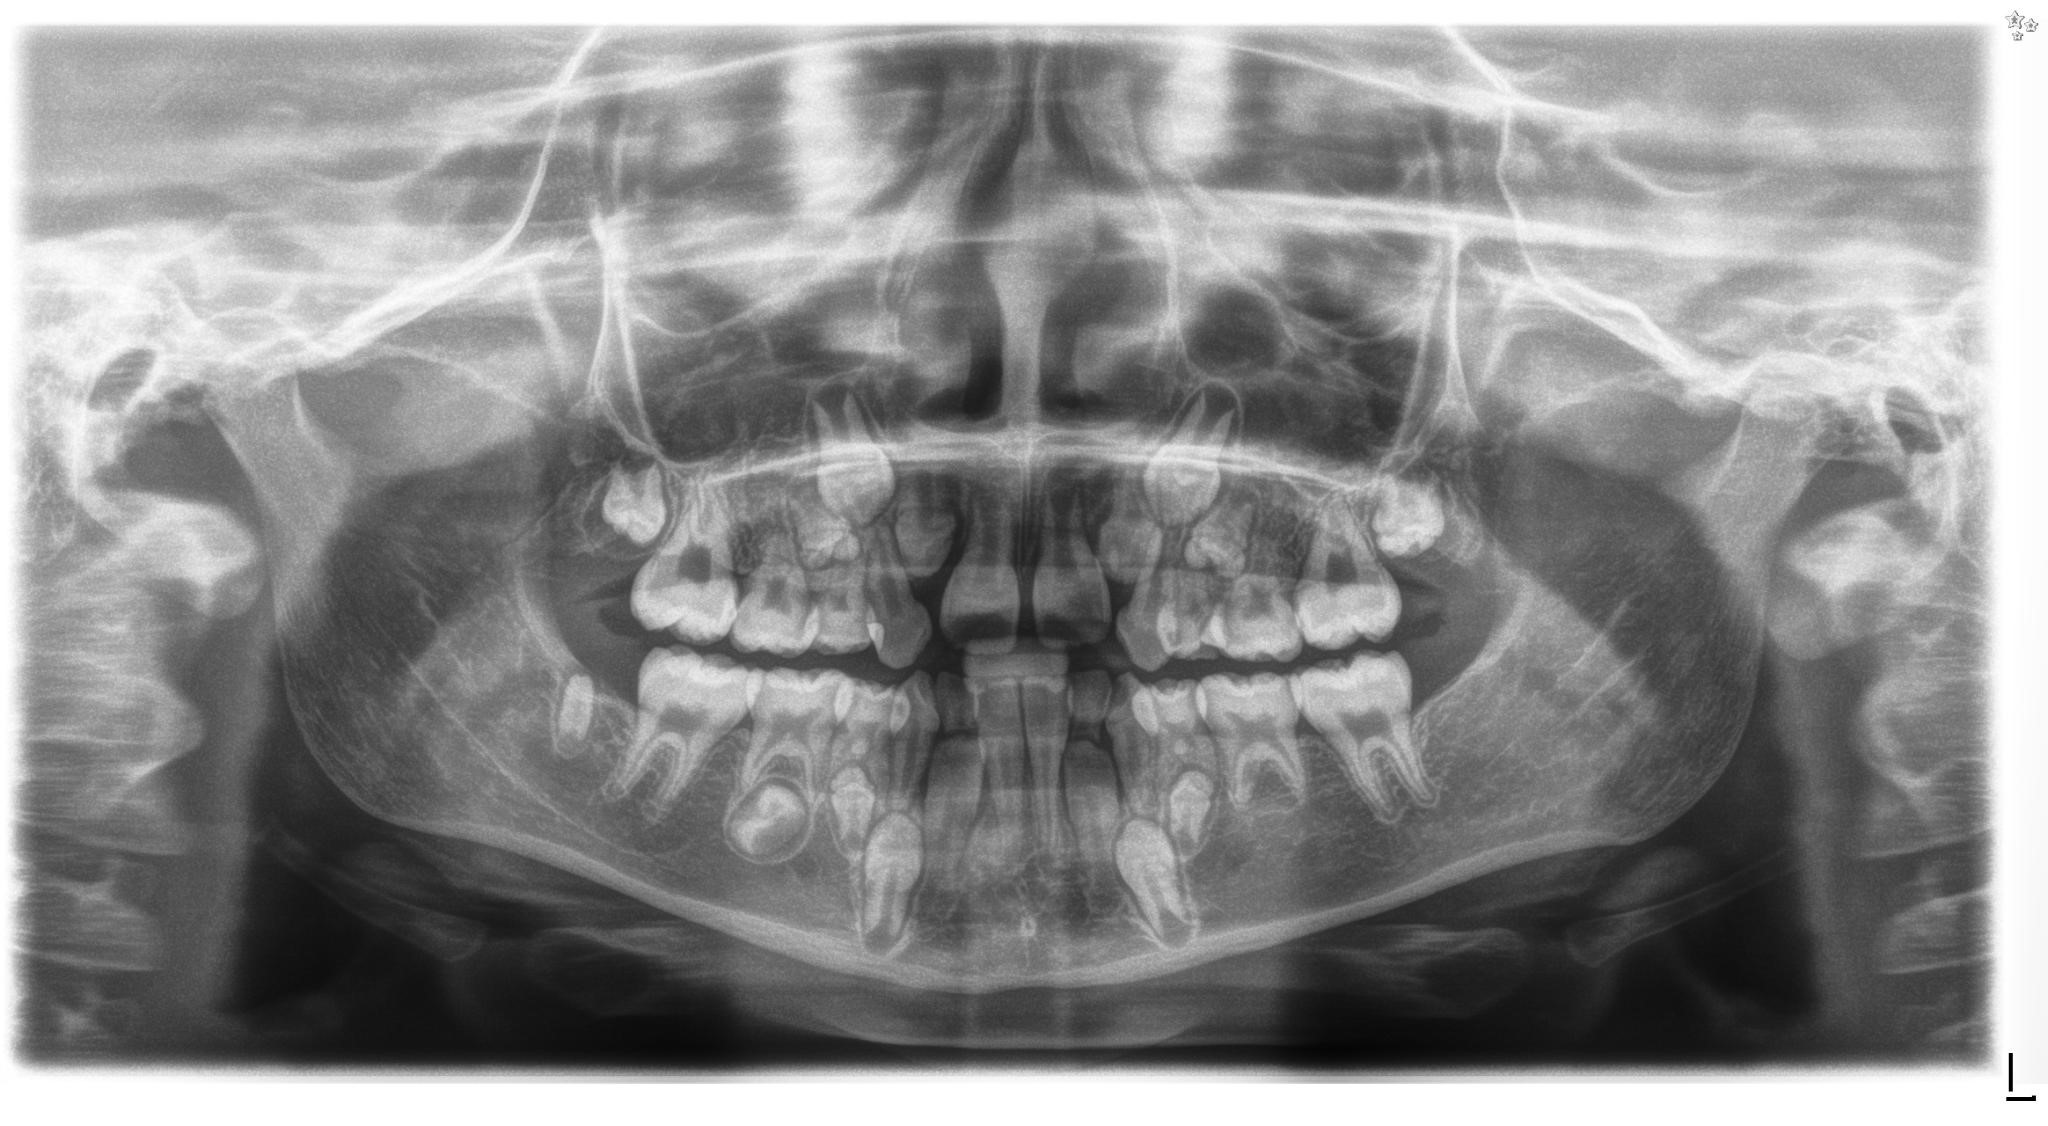

Challenges in orthodontic treatment of patients after childhood cancer disease – a literature review

Joanna Maciejewska

, Bogna Racka-Pilszak

https://doi.org/10.31373/ejtcm/208477

43-57